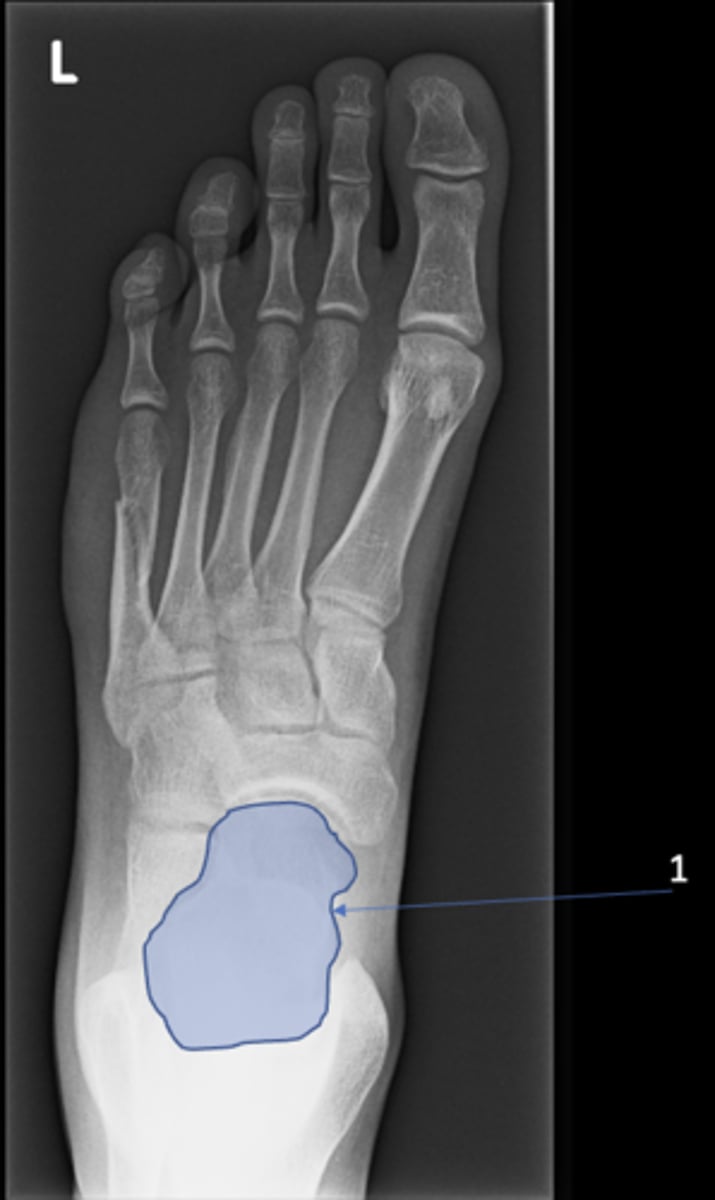

New cards

Left inferior pubic ramus

ID 15

<p>ID 15</p>

15

S1 tubercle

ID 16

<p>ID 16</p>

16